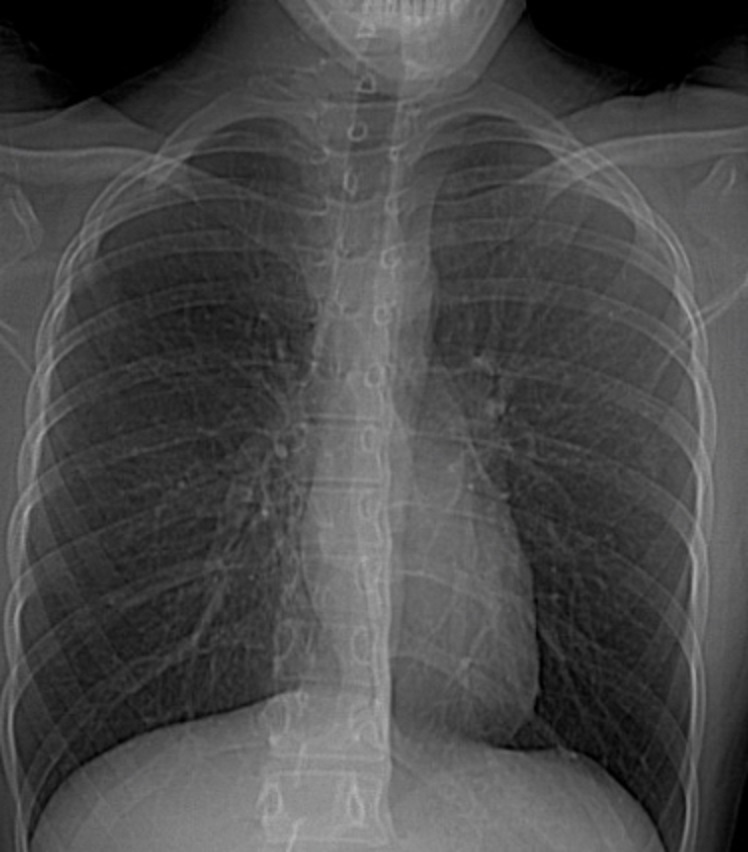

Image

radiologique standard PA pulmonaire de lyse costale

droit d'une lesion metastase costale |

Cliche de face PA d'une

syndrome de Poland avec de hypolasia du muscle

pectoralis majeur droit . Ce qui donne une aspect

radiologique est hyperluscence du 1/2 superieure du

champ pulmonaire droit |